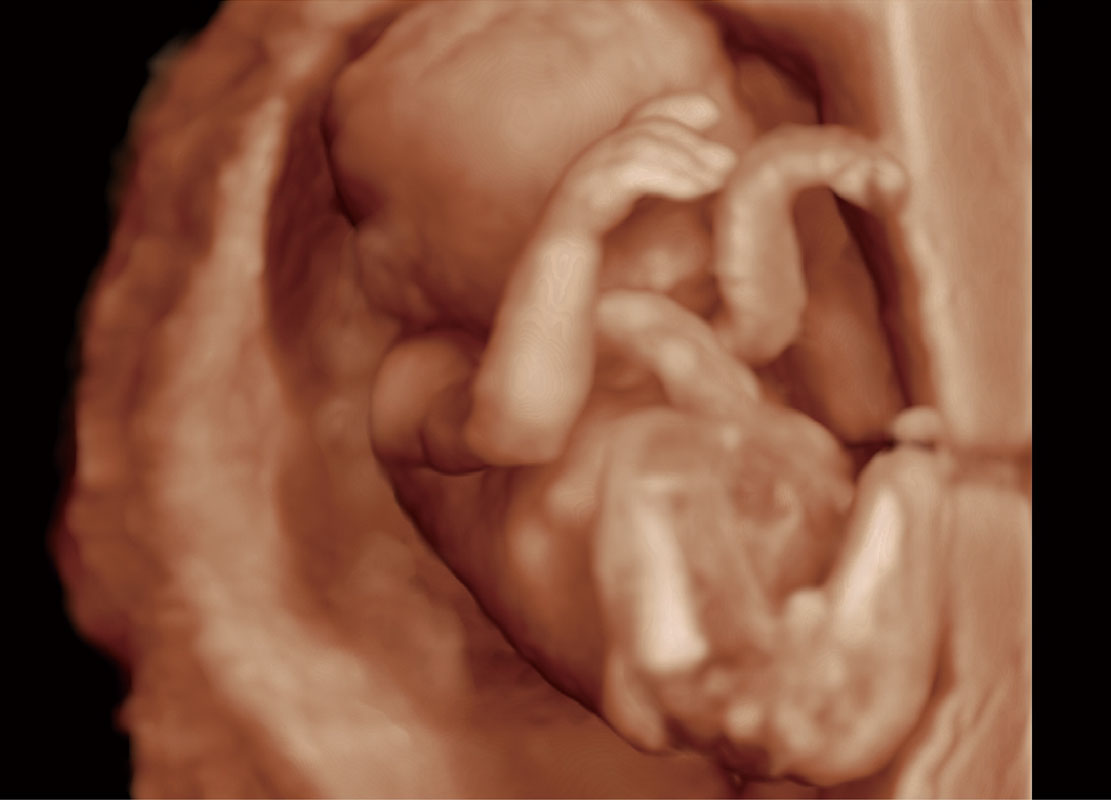

中晚孕筛查

P60提供简单易学易用的高端诊断工具,为您中晚孕筛查提供快速清晰的解剖信息。

S-Fetus(acq.)

& S-Fetus(meas.)

S-Fetus

S-Fetus能够助您在实时扫查过程中自动识别标准切面、自动测量并录入报告。一个按键,即可快速、高效地获取胎儿生理指标,简化您的产科检查操作。